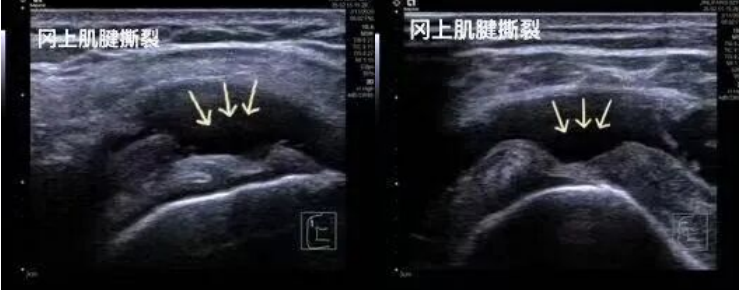

1.運(yùn)動(dòng)損傷:肩袖撕裂、網(wǎng)球肘、跟腱斷裂、肌肉拉傷等。

2.高分辨率與實(shí)時(shí)動(dòng)態(tài)成像:超聲波可捕捉毫米級(jí)的軟組織細(xì)節(jié)(如肌腱纖維的撕裂、滑膜增生),并能實(shí)時(shí)顯示關(guān)節(jié)屈伸、肌肉收縮等動(dòng)態(tài)過(guò)程,輔助醫(yī)生精準(zhǔn)評(píng)估功能異常。